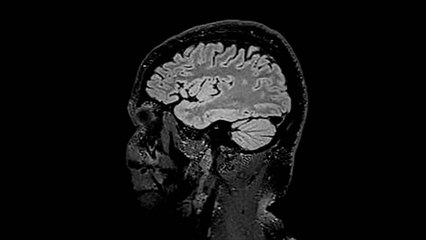

The study looked at how experiences affect how the body develops.